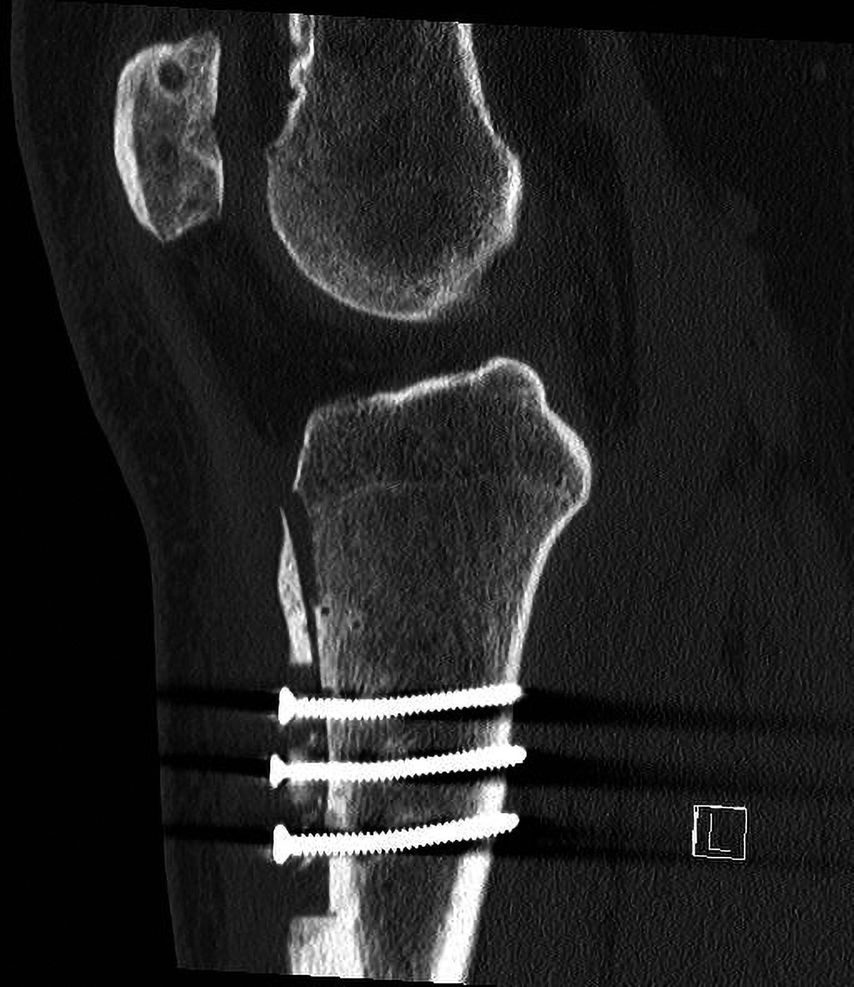

17-jähriger Patient mit wiederkehrenden Patellaluxationen

Aufgrund eines erhöhten Caton-Deschamps-Index von >1,2 erfolgten die Tuberositasdistalisierung und die MPFL-Plastik mit der Gracillissehne (Abb. 2 und 3). Ca. 4 Wochen nach dem operativen Eingriff stürzte der Patient auf das rechte Kniegelenk mit Mehrfragmentbruch des Tuberositasfragments (Abb. 4). Die neuerliche Fixierung erfolgte mittels 3,5mm-Drittelrohrverplattung sowie, wegen des Mehrfragmentbruches im proximalen Bereich, mittels Durchflechtungsnaht und Knochenankern (Abb. 5).